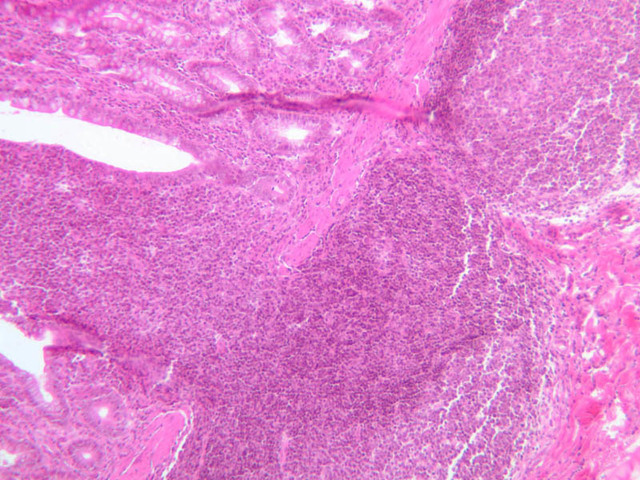

Lymph Nodes

When foreign substances or antigens get into body tissues, such materials are usually taken into the lymph and transported to aggregations of lymphoid tissue called lymph nodes (slide A-32, H&E [2.5x-labeled, 10x, 20x, 40x] [2.5x-labeled, 10x, 20x] [2.5x, 10x, 20x-labeled, 40x]; A-33, H&E [2.5x, 10x, 20x, 40x]; A-34, retic [2.5x, 10x, 20x, 40x-labeled]; A-35, H&E [2.5x, 10x, 20x, 40x]), which are composed of lymph nodules invested by a distinct connective tissue capsule. The node is visibly separable into a cortex, where the densely stained nodules are concentrated, and a light staining medulla (A-32 [2.5x, 10x-labeled, 20x, 40x]). Strands, or trabeculae, of connective tissue separate the node into cortical compartments and join centrally in the node to emerge at the indented side known as the hilus. Small arteries and veins enter and leave the node at the hilus, being distributed in the node through the trabeculae. Capillary branches from the arteries are spread throughout the lymphoid node. Multiple afferent lymphatic vessels penetrate the capsule of the node, emptying into a subcapsular sinus which is a relatively cell-free zone (A-32 [2.5x, 10x, 20x, 40x-labeled]). Unidirectional flow of lymph from the afferent lymphatics into the sinus is assured by the valves in the vessels. From the subcapsular sinuses, lymph percolates through the relatively unobstructed cortical sinuses to the medulla. During this flow the lymph is filtered by phagocytes and foreign antigens are presented to lymphocytes by dendritic cells, the resident antigenpresenting cells. Nodules are formed as needed and subsequently disappear. Lymph finally reaches the medullary sinuses bounded by wide cords of tissue and passes out of the node at the hilus through the sole efferent lymphatic vessel.

The lymphoid tissue of a node is thus divisible into the nodules in the cortex and looser cords in the medulla. In the cortex, carefully examine a secondary nodule, composed of a dense outer rim of cells and a more loosely organized core (germinal center). In between the nodules find larger cells with pale, oval nuclei. These are reticular cells and will be most easily identified in the reticular-stained preparation (A-34 [2.5x, 10x, 20x, 40x] [10x, 20x, 40x]). The reticular fibers cells make up the CT scaffolding of the lymph node. Note that there are fewer reticular fibers in the germinal centers. Medium-sized cells with pale nuclei, particularly cells with a prominent nucleolus, may be progenitor cells of new lymphocytes. Macrophages present in the nodule are hard to distinguish unless they contain phagocytosed material. In the medulla, cell types in the cords are easier to distinguish because cytoplasmic size and extent can be seen. For example, the differences between large lymphocytes and reticular cells can be seen. Several types of granular leukocytes are frequently found in the cords in addition to the expected population of lymphocytes and plasma cells.